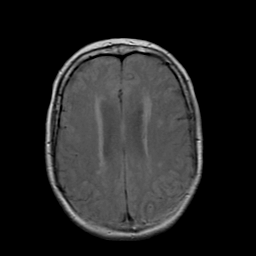

Stroke: proton density-weighted MR #2 -- Slice #16

[Home][Help][Clinical] Slice 16